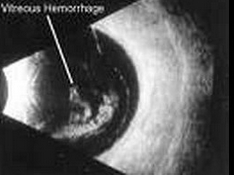

10、单项选择题

患者,女,14岁,眼部外伤两小时。超声检查如图,最可能的诊断为()

A.玻璃体积血

B.玻璃体混淆

C.脉络膜脱离

D.视网膜脱离

E.以上均不是